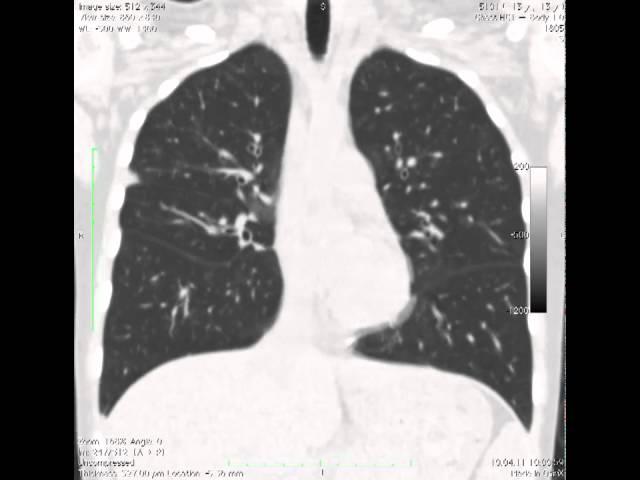

здравствтуйте, подскажите пожалуйста, на флюорографии и рентгене легких у моего брата непонятная картина, подозревалим туберкулез, "метатуберкулезные изменения", "диссеминированный процесс в легких, инфильтраты" ( все под вопросом, пцр тест отрицательный, предлагают сделать кт, брату нельзя облучаться ( родился в зоне радиации, и аутоимунное заболевание). Хотим сейчас в частном порядке сделать сначала мрт легких ( у нас в городе делают) подскажите пожалуйста, насколько такое обследование будет информативным, позволит ли оно исключит метастазы в том числе, и подтвердить отсутствие именно туберкулезных изменений, заранее спасибо вам за ответ!